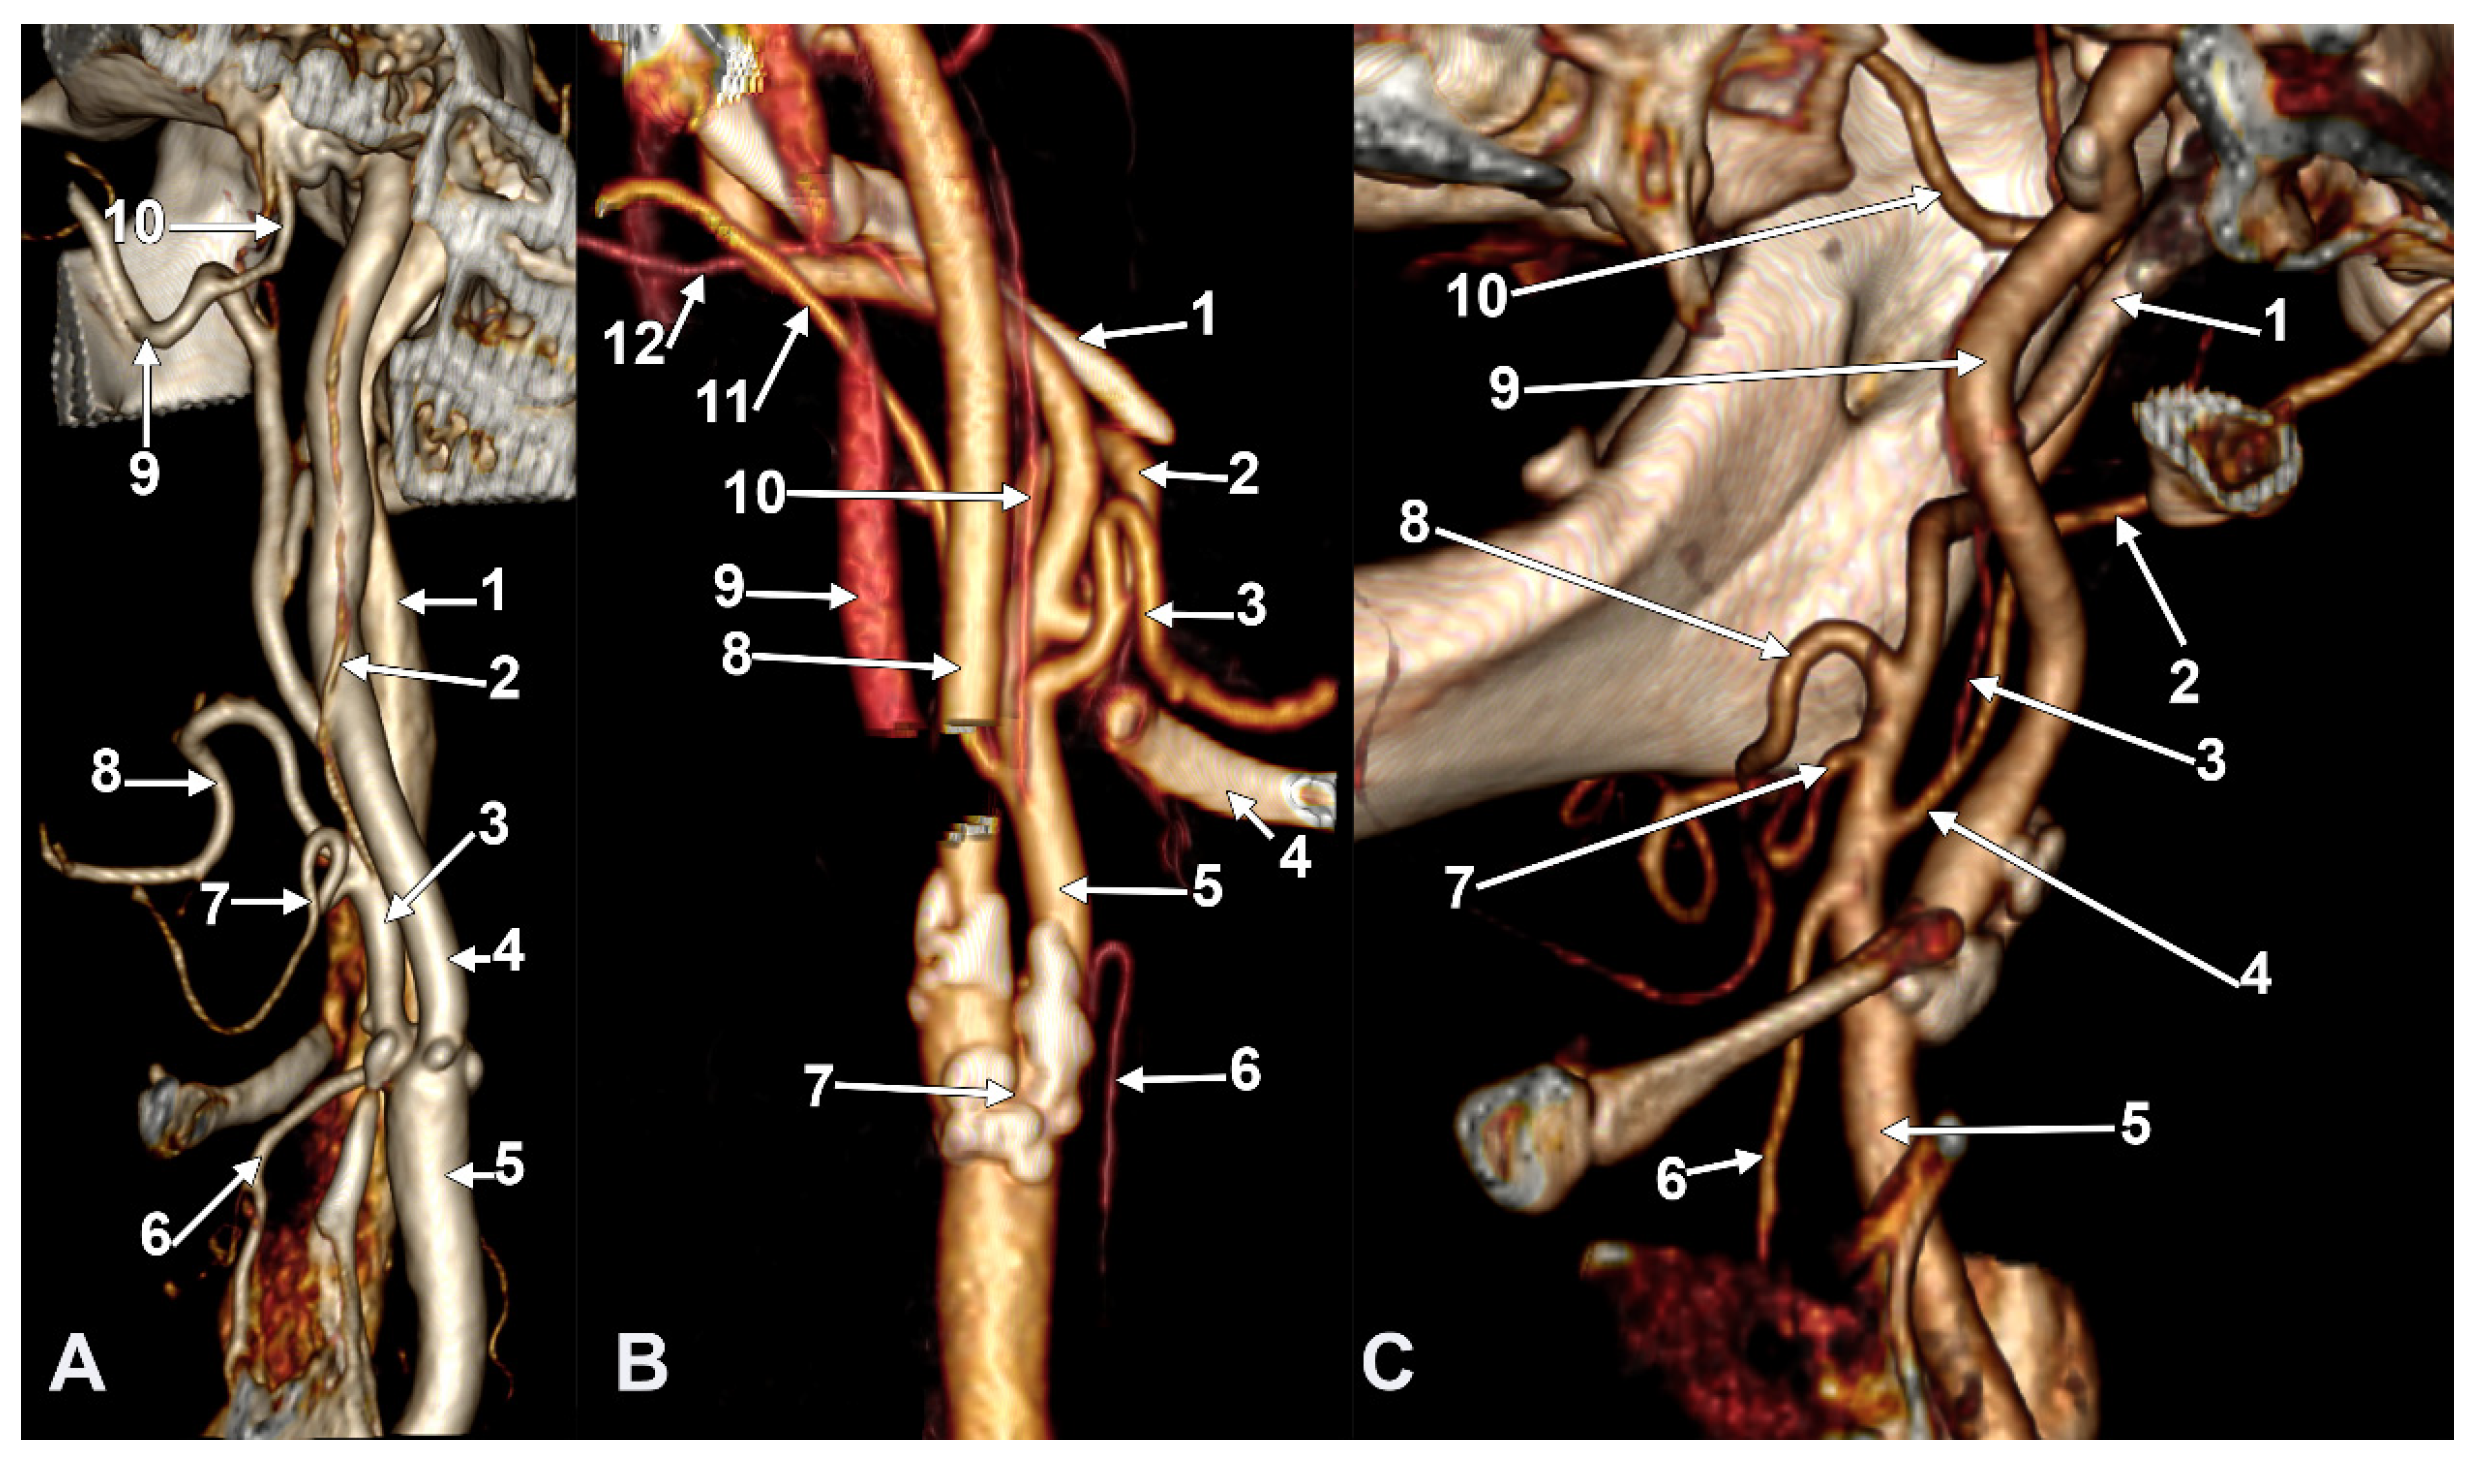

Figure 8. Long inferior petrosal sinus (arrowheads). Internal carotid origin of the ascending pharyngeal artery. Right side. (A) Anterolateral view. (B) Anteromedial view. 1. Common carotid artery; 2. internal jugular vein; 3. internal carotid artery; 4. external carotid artery; 5. superior thyroid artery; 6. lingual artery; 7. facial artery; 8. ascending pharyngeal artery; 9. styloid process; 10. body of the hyoid.

Figure 9. Thyrolingual trunk originating from the common carotid artery. The ascending pharyngeal artery is the first branch of the external carotid artery. Type 33 of the sequence of branches of the external carotid artery. Three-dimensional rendering. Left side. (A) Posteromedial view. (B) Antero-lateral view. 1. Common carotid artery; 2. greater hyoid horn; 3. thyrolingual trunk; 4. internal carotid artery; 5. ascending pharyngeal artery; 6. external carotid artery; 7. superior thyroid artery; 8. lingual artery; 9. facial artery; 10. styloid process; 11. ossified stylohyoid ligament.

On the right side (Figure 7 and Figure 8), a 4.23 cm long styloid process was found, with a medial inclination of 72.4°. It crossed anteriorly, above the transverse process of the atlas, two veins: laterally—the internal jugular (IJV) vein, which had a transverse diameter of 5.94 mm, and medially—a long inferior petrosal sinus (IPS), with a transverse diameter of 3.15 mm. The IJV continued laterally to the transverse process of the atlas, and the inferior petrosal sinus, anterior to it. It was observed that the compression of the IJV occurs between the transverse process of the atlas and the posterior aspect of the digastric muscle. Also, the IPS appeared compressed at this level. The IJV had a minimum diameter of 1.21 mm, and the IPS had a minimum diameter of 1.08 mm. The IPS crossed laterally the ICA and APA, which, in turn, originated from the ICA (type IV), and continued medial to the ECA, crossed the origin of the FA, and descended anterior to the ECA, over the initial loop of the LA. The IPS and ECA coursed on the lateral side of the greater hyoid horn. Inferior to the hyoid, the IPS crossed the STA laterally and continued obliquely posteroinferiorly over the CCA, emptying into the IJV at 3.59 cm inferior to the CB. The APA on that side arose from the anteromedial wall of the origin of the ICA, at the hyoid level.

On the left side (Figure 9), the APA originated 8.9 mm posterosuperior to the tip of the greater hyoid horn from the posterior wall of the origin of the ECA, as its first branch. This was because the LA and STA arose via a common TLT from the CCA. The TLT origin was 8.8 mm inferior to the greater hyoid horn; the length of this common arterial trunk was 5.1 mm. It divided at 5 mm lateral to the superior horn of the thyroid cartilage into two vertical branches—an upper one, the LA, which ascended over the greater hyoid horn and made an upper loop before continuing with the hyoglossal segment, and a second, inferior one, the STA.